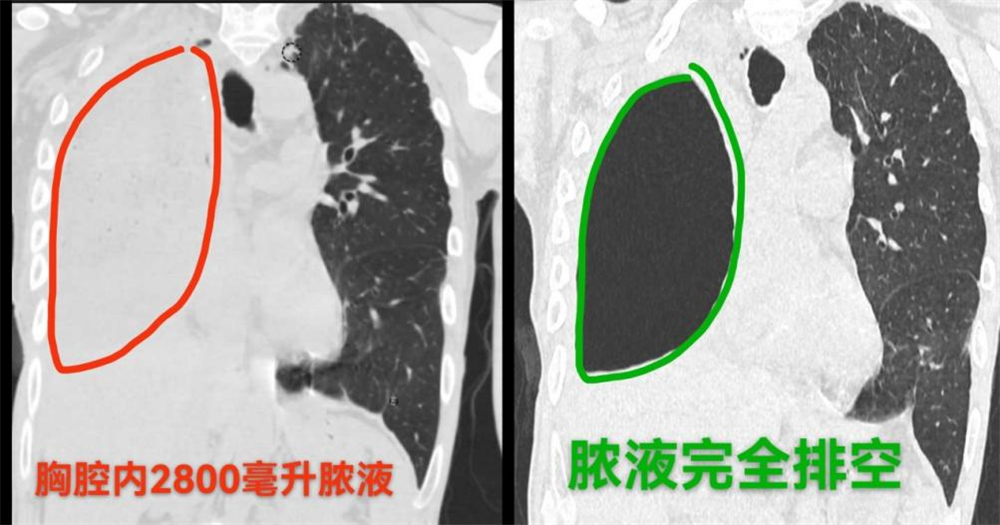

接诊后,胸外科王文瑀主任深知病情疑难危重,随即牵头组织电诊科、消化科、临床营养科等科室开展MDT多学科会诊,为患者制定个体化治疗方案:一是联合电诊科实施胸腔双通路引流手术,采用“冲洗+引流”同步的改良治疗方式,精准清除胸腔内2800毫升脓液,在控制感染源头的同时,最大程度保护患者残存左肺功能及身体结构;二是针对患者严重营养不良状况,临床营养科制定“一人一方”精准营养计划,通过静脉与肠道双管齐下提供营养支持;三是护理团队同步提供精细照护与心理疏导,助力患者康复。

经综合治疗,患者感染迅速得到控制,体温恢复正常,精神、食欲逐步改善,体重稳步增加,康复速度远超预期,短时间内即达到出院标准。相较于此前多家医院提出的创伤较大的开胸手术及数十万高昂费用,此次治疗的微创优势显著,总花费也低于患者及家属的心理预期。